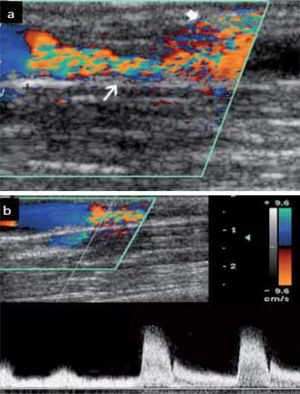

Cuando registramos una curva, ésta debe tener una adecuada variabilidad, lo que traduce permeabilidad del eje venoso desde el sitio del examen hasta el diafragma y corazón (Fig 14a)

a.- Curva a nivel de vena axilar derecha, con adecuada variabilidad b.- Curva a nivel de vena axilar izquierda, con pérdida de variabilidad lo que nos hace sospechar oclusión proximal c.- Trombosis aguda completa de la vena subclavia, responsable del aplanamiento de la curva axilar. Presencia de catéter endovascular (flecha).

Cuando la curva pierde esta variabilidad y se hace plana, se debe sospechar estenosis u oclusión del eje hacia el corazón (4) (Fig 14 b y c).